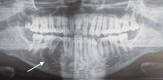

Odontogenic fibromyxoma (OFM) is an uncommon benign neoplasm originating from the odontogenic ectomesenchyme. It exhibits a slow-growing yet locally aggressive behavior, most frequently presenting in young adults, although it can occur at any age and shows no significant gender predilection. Despite its clinical relevance, current research provides limited information regarding the risk factors, causative agents, and molecular pathways that contribute to its development and aggressive behavior. We present a case of OFM located in the mandible of a 38-year-old African male who reported a painless swelling in the right mandible extending from the first premolar to the second premolar. The clinical examination revealed a limited, firm, painless vestibular swelling in the region of teeth 44 and 45. The affected teeth exhibited normal vitality and physiological mobility. Radiographic imaging demonstrated a multilocular radiolucency with a "soap bubble" appearance, without evidence of root resorption. Histopathological analysis confirmed the diagnosis of odontogenic fibromyxoma, showing a proliferation of fibroblasts and myofibroblasts within a loose, myxomatous stroma rich in acid mucopolysaccharides, with scattered stellate cells displaying minimal pleomorphism. This case underscores the importance of a comprehensive diagnostic approach that integrates clinical, radiological, and histopathological findings to accurately identify OFM and distinguish it from other similar jaw lesions. Although conservative treatments such as enucleation with curettage offer notable benefits, the ideal surgical approach and follow-up protocol remain subjects of ongoing investigation. A more profound understanding of OFM's underlying pathogenesis could lead to improved treatment outcomes and guide future research on targeted therapeutic strategies.